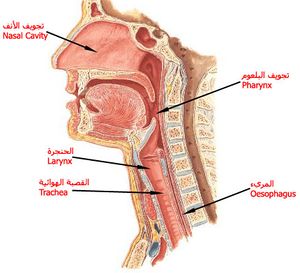

الحنجرة (بالإنجليزية : Larynx) هي الجزء الأمامي من العنق, عريضة من أعلى, مثلثة الشكل, وتتكون من عدة غضاريف تتحرك بوساطة عضلات مبطنة بغشاء مخاطي, يمتد في تجويفها الحبلان الصوتيان, حيث ينتج الصوت عن طريق الهواء المدفوع من الرئتين ليذبذب الأحبال الصوتية. ويحرس مدخل الحنجرة زائدة غضروفية تسمى لسان المزمار, له دور مع حركة الحنجرة عند الإبتلاع.

الرقبة: حلق - حنجرة – تفاحة آدم